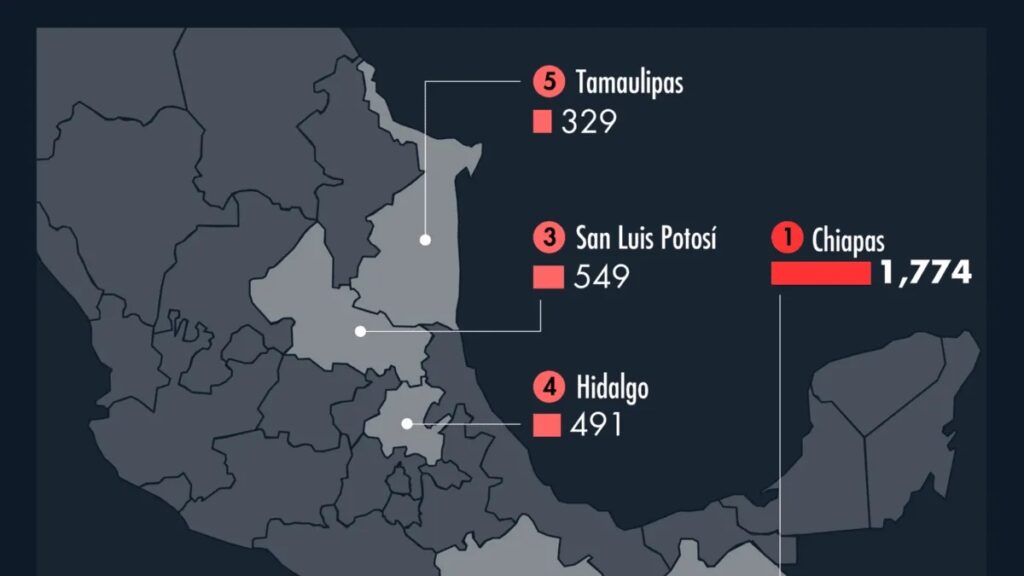

Confirman dos casos humanos de miasis por gusano barrenador en Chiapas; Oaxaca en alerta sanitaria

La Secretaría de Salud ha confirmado dos casos de miasis humana causada por el gusano barrenador (Cochliomyia hominivorax) en el estado de Chiapas. Hasta la fecha, no se han reportado contagios en personas en Oaxaca, aunque las autoridades sanitarias mantienen una vigilancia epidemiológica activa en la región. Casos confirmados en Chiapas El primer caso se […]

Alerta sanitaria en México: Casos de sarampión aumentan a 421; Oaxaca reporta cuatro infecciones

Ciudad de México, 20 de abril de 2025 — México enfrenta un preocupante repunte de sarampión, con 421 casos confirmados hasta la semana epidemiológica 15, según el Comité Nacional para la Vigilancia Epidemiológica (Conave). El estado de Chihuahua concentra el 95.7% de los casos, con 403 infecciones, mientras que Oaxaca ha reportado cuatro casos, todos […]

Cuáles son los estados de México donde se han detectado más casos de tos ferina y por qué es peligrosa

Esta enfermedad es altamente contagiosa con un periodo de incubación de 7 a 10 días Crédito: Jesús Aviles / Infobae México La tos ferina es una enfermedad que va en aumento en México desde el pasado mes de febrero según el constante monitoreo por parte de la Secretaría de Salud. Debido a que se trata de una […]